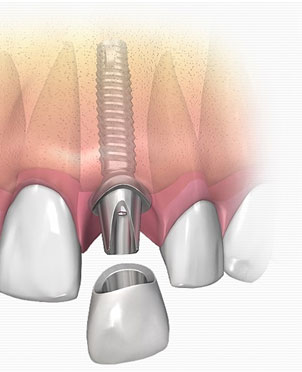

The success rate of a dental implant is incredibly high. It is placed under local anaesthesia by our implant surgeons, and is then allowed to heal and integrate with the bone.

Once healed, it is then restored with a crown.